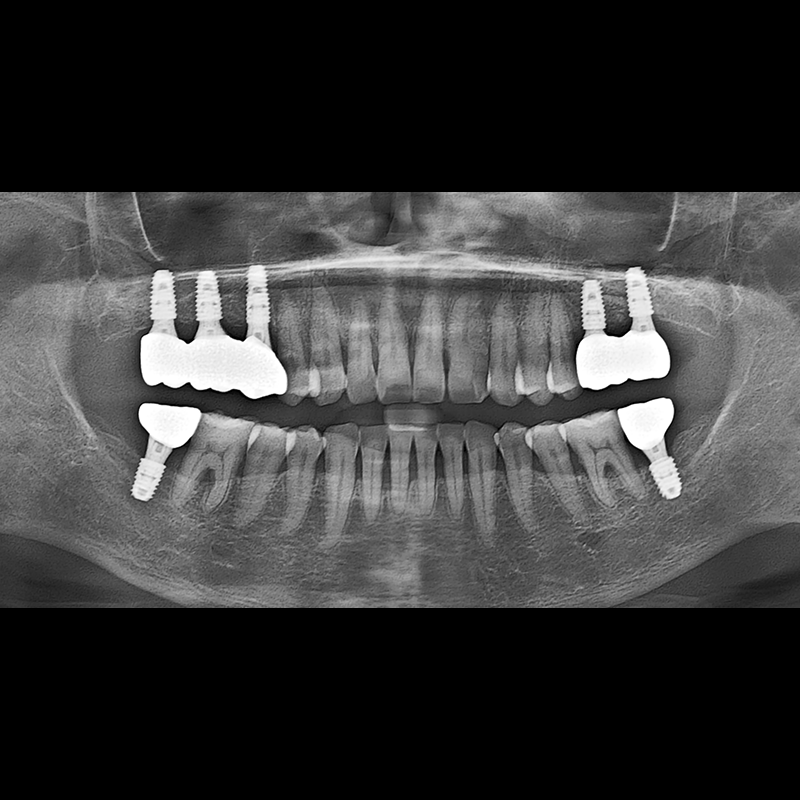

BEFORE AFTER

임플란트 전후사진 2025.05.30

결손된 치아 부분과 살리기 힘든 치아 위치에 임플란트를 식립하였습니다.